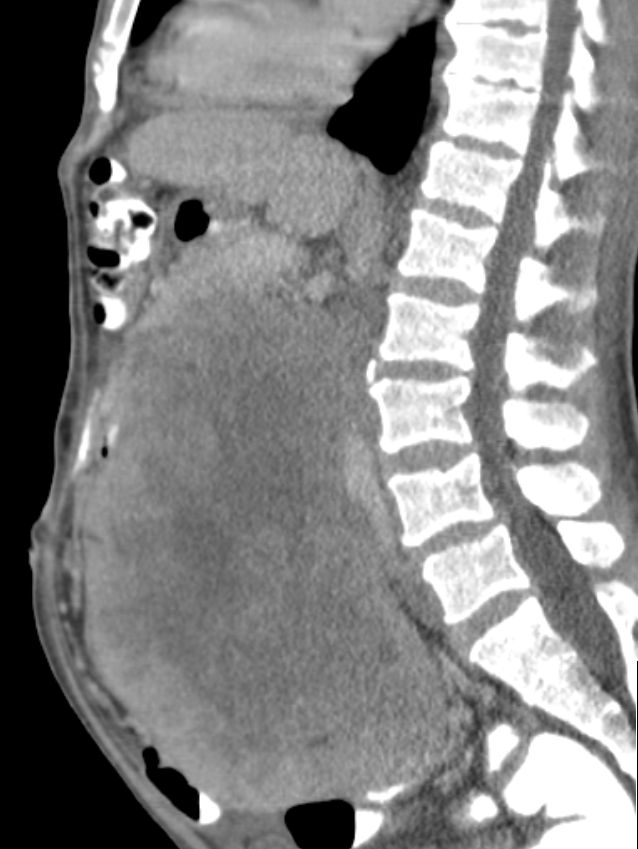

| retroperitoneal | 43-jähriger Mann mit großer Raumforderung im Abdomen.

Undifferenziertes Weichteilsarkom.![]() |